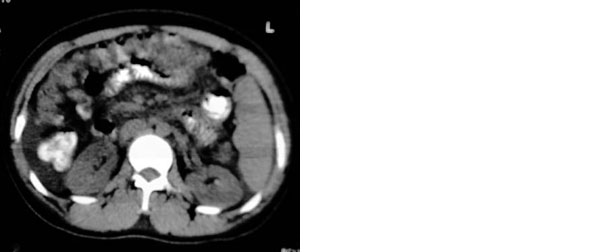

患者:女,43岁,自觉全身肿胀8个多月。b超提示:肝硬化、腹水,胆囊炎。胰、脾、肾未见明显异常。

肝脏体积变小,左右比例失调,右肝变小较剧,脾脏增厚,腹水征象明显考虑肝硬化、腹水

肝脏体积缩小,左右肝比例失调,轮廓不规整,肝裂增宽,肝周见新月形液性密度影,脾脏增厚.应诊断为肝硬化,腹水,脾大.